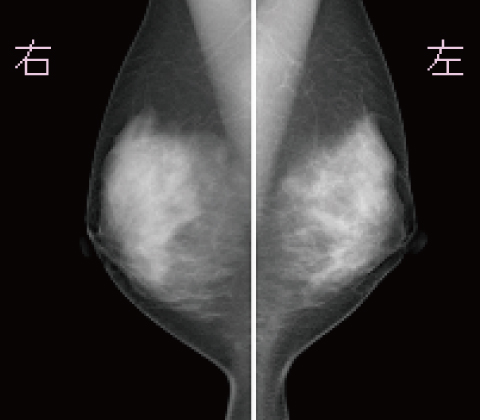

乳房画像

MLO

CC